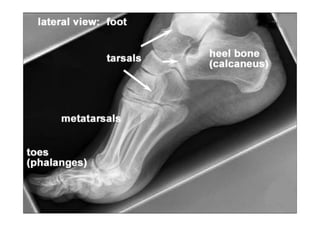

RADIOLOGIA DO

TRAUMA DO ESQUELETO

Referência: http://www.accessexcellence.org/RC/VL/